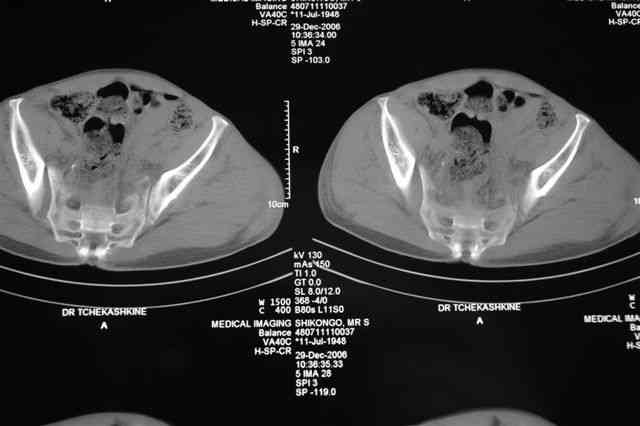

По-поводу фиксации таза спонгиозными винтами. Данный способ все-таки показан для фиксации повреждения крестцово-подвздошного сочленения или переломов крестца. Мне кажется, что в данной случае ситуация иная - имеется перелом "основания" крыла подвздошной кости (в который вовлечена и поверхность, составляющая крестцово-подвздошное сочленение). Не уверен, что фиксация данного повреждения (и заднего полукольца) винтами будет стабильной, так как именно на уровне 1-2 крестцовых позвонков (где обычно вводят винты) линия перелома уходит в латеральном направлении от крестцово-подвздошного сочленения.

PI>По-поводу фиксации таза спонгиозными винтами. Данный способ все-таки показан

для фиксации повреждения крестцово-подвздошного сочленения или переломов крестца. Мне кажется, что в данной случае ситуация иная - имеется перелом

"основания" крыла подвздошной кости (в который вовлечена и поверхность, составляющая крестцово-подвздошное сочленение). Не уверен, что фиксация данного повреждения (и заднего полукольца) винтами будет стабильной, так как

именно на уровне 1-2 крестцовых позвонков (где обычно вводят винты) линия перелома уходит в

латеральном направлении от крестцово-подвздошного сочленения.

Я просмотрел томограммы и у меня создалось впечатление, что винтам есть за что *зацепиться*. В сочетании с 5 мм Шанц винтами, проведенными через нижне-переднюю ость спереди назад через КП сочленения -стабильность тазового кольца должна восстановиться. - Это , конечно, при условии , что закрытая рнепозиция будет успешной.

после КТ отказался от этой идеи - двусторонний перелом крестца в зоне 1 - алярная часть, при попытке низведения правого гемипелвиса теоретически есть вероятность смещения

фрагмента крестца слева.